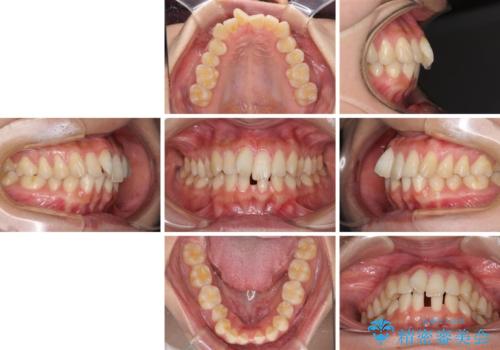

- 下顎前歯の欠損により隙間ができていることを気にして来院された患者様です。

下顎前歯が2歯欠損しており、スペースになっており、上顎は叢生歯列となってしました。

奥歯の咬み合わせを考えると、理想的には2歯、最低でも1歯は下顎前歯の欠損部にインプラントやブリッジにより歯数を増やす必要がありました。

周囲の歯を削らないようにするためインプラントがおすすめとなりますが、歯根の移動が不十分な場合にはインプラントを埋入する幅が獲得できないため、その場合にはオールセラミックブリッジにより補綴治療を行うこととして、矯正治療を行うこととしました。